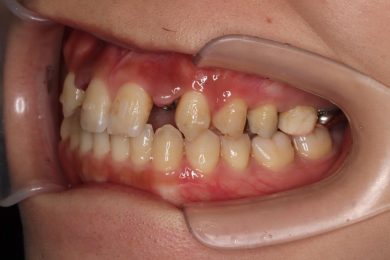

先天性欠如による上顎前歯欠損部にインビザライン術前矯正とインプラントを埋入した症例

初診時・インプラント・終了時